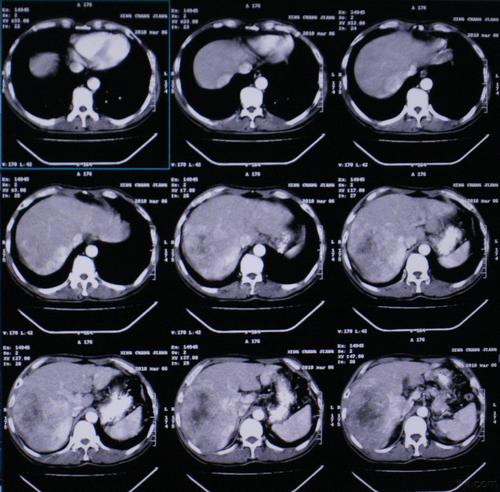

CT是用X射线束对人体某部一定厚度的层面进行扫描,由探测器接收透过该层面的X射线,转变为可见光后,由光电转换变为电信号,再经模拟/数字转换器(analog/digital converter)转为数字,输入计算机处理。图像形成的处理有如对选定层面分成若干个体积相同的长方体,称之为体素(voxel)。

扫描所得信息经计算而获得每个体素的X射线衰减系数或吸收系数,再排列成矩阵,即数字矩阵(digital matrix),数字矩阵可存贮于磁盘或光盘中。经数字/模拟转换器(digital/analog converter)把数字矩阵中的每个数字转为由黑到白不等灰度的小方块,即像素(pixel),并按矩阵排列,即构成CT图像。所以,CT图像是重建图像。每个体素的X射线吸收系数可以通过不同的数学方法算出。

CT的工作程序是这样的:它根据人体不同组织对X线的吸收与透过率的不同,应用灵敏度极高的仪器对人体进行测量,然后将测量所获取的数据输入电子计算机,电子计算机对数据进行处理后,就可摄下人体被检查部位的断面或立体的图像,发现体内任何部位的细小病变。